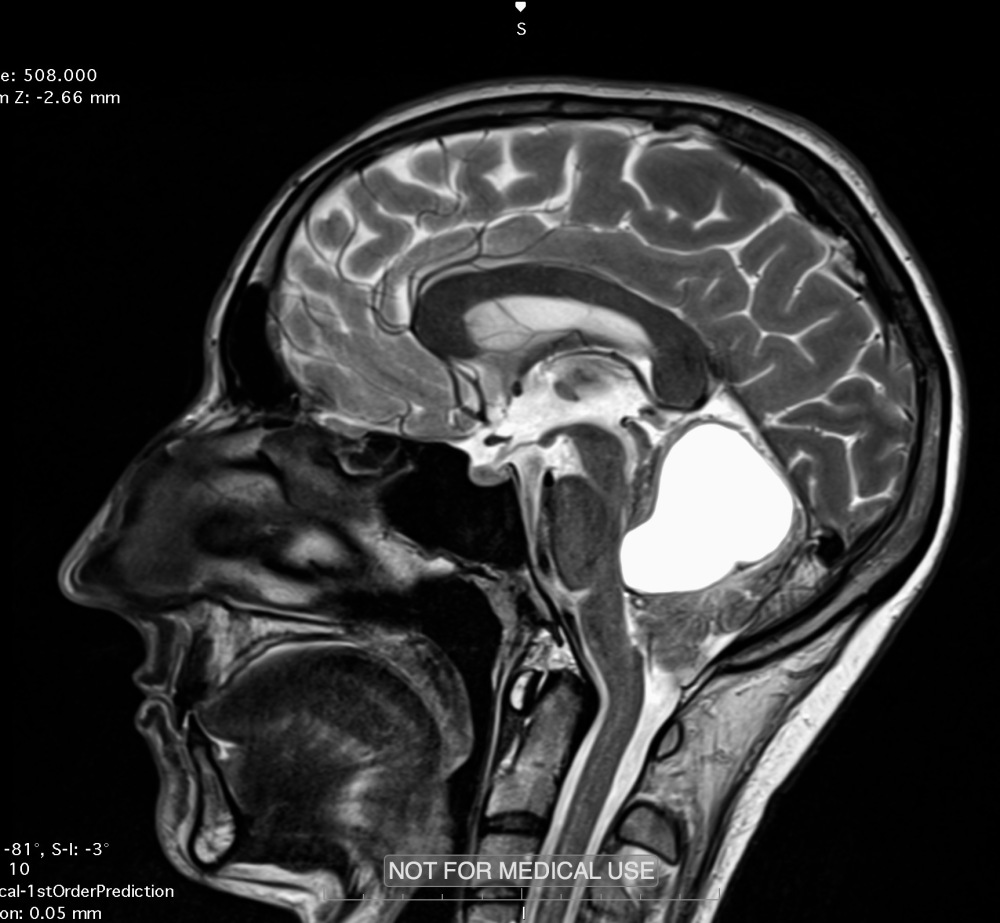

W styczniu 2018 roku wykryto u Niego guza mózgu, a po kilku dniach, dzięki staraniom członków zespołu, trafił do szpitala w Bydgoszczy, pod opiekę profesora Marka Harata, tzw. „specjalisty od cudów”.

Cud się rzeczywiście wydarzył, bo Bartek operację przeżył, pomimo 2% szans, jakie Mu dawano. Oprócz guza, w mózgu utworzył się ropień, który podczas operacji rozlał się do głowy i płuc. Po operacji nastąpiły ogromne komplikacje, Bartek w jej trakcie doznał udaru niedokrwiennego na skutek obrzęku mózgu, pojawiła się też sepsa i paraliż jednej strony ciała. Bartek zaległ w łóżku bez ruchu, bez zdolności mówienia, mozolnie wydobywając się do życia.